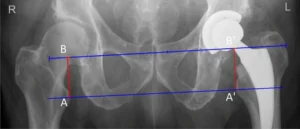

Lunghezza dell’arto e offset femorale

La radiografia post-operatoria consente una valutazione preliminare della lunghezza dell’arto operato e del ripristino dell’offset femorale. Alterazioni significative di questi parametri possono avere ripercussioni funzionali importanti, influenzando la biomeccanica dell’anca, la deambulazione e la soddisfazione del paziente.

È importante sottolineare che la valutazione radiografica deve essere sempre integrata con l’esame clinico, poiché piccole differenze radiografiche possono non essere clinicamente rilevanti e viceversa.